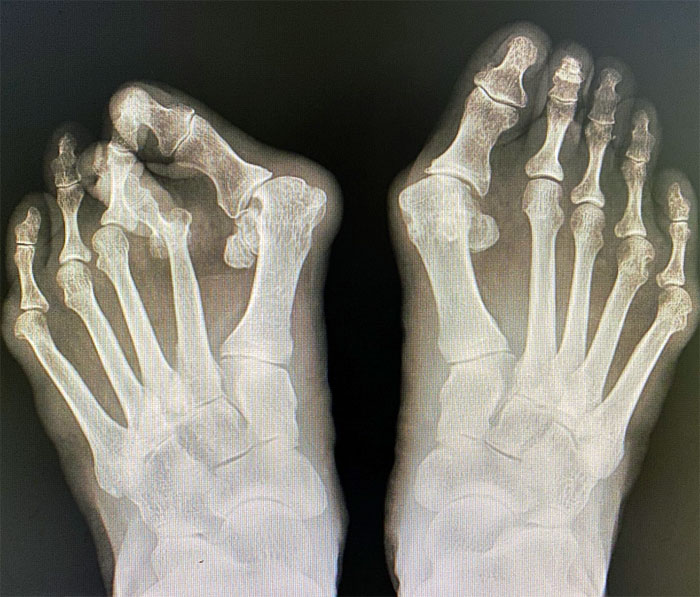

무지외반증(Hallux valgus)은 엄지발가락이 둘째 발가락 쪽으로 심하게 휘어지면서 엄지발가락과 관절을 이루는 첫 번째 중족골이 안쪽으로 치우쳐지는 변형을 의미합니다. 이로 인해 발 앞쪽이 넓어지거나 더 튀어나오게 되어 통증과 미용적 문제를 초래할 수 있습니다. 무지외반증은 주로 여성에게 발생하며, 젊은 연령대에서도 흔히 볼 수 있습니다. 초기 증상은 발의 형태 변화와 함께 발가락의 통증이 동반됩니다. 심한 경우에는 보행에도 영향을 줄 수 있습니다.

- X-선 검사 : 발의 구조를 확인하기 위해 X-선을 촬영하여 변형 정도를 평가합니다.